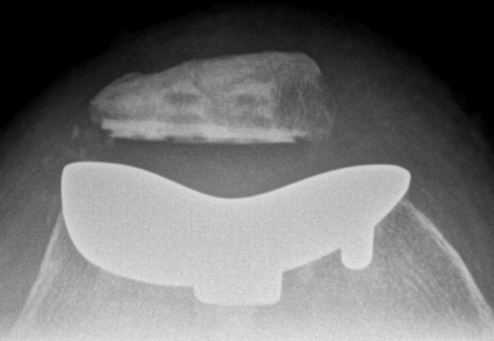

Patellofemoral joint replacement

Technique